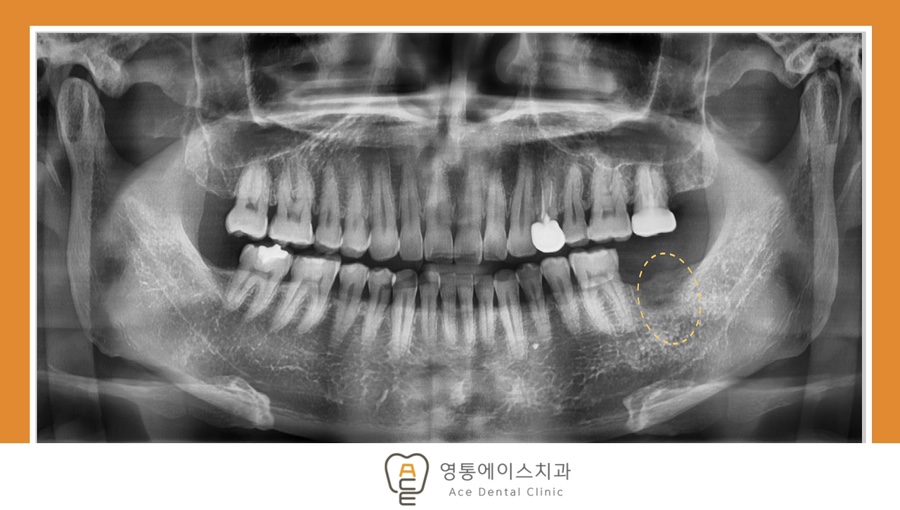

치료 전 사진 / 2024. 11. 26

따라서 치료 전에는 정밀 검사를 통해 잇몸뼈의 양과 높이, 신경 위치, 주변 치아 상태 등을 꼼꼼히 확인하는 것이 중요합니다.